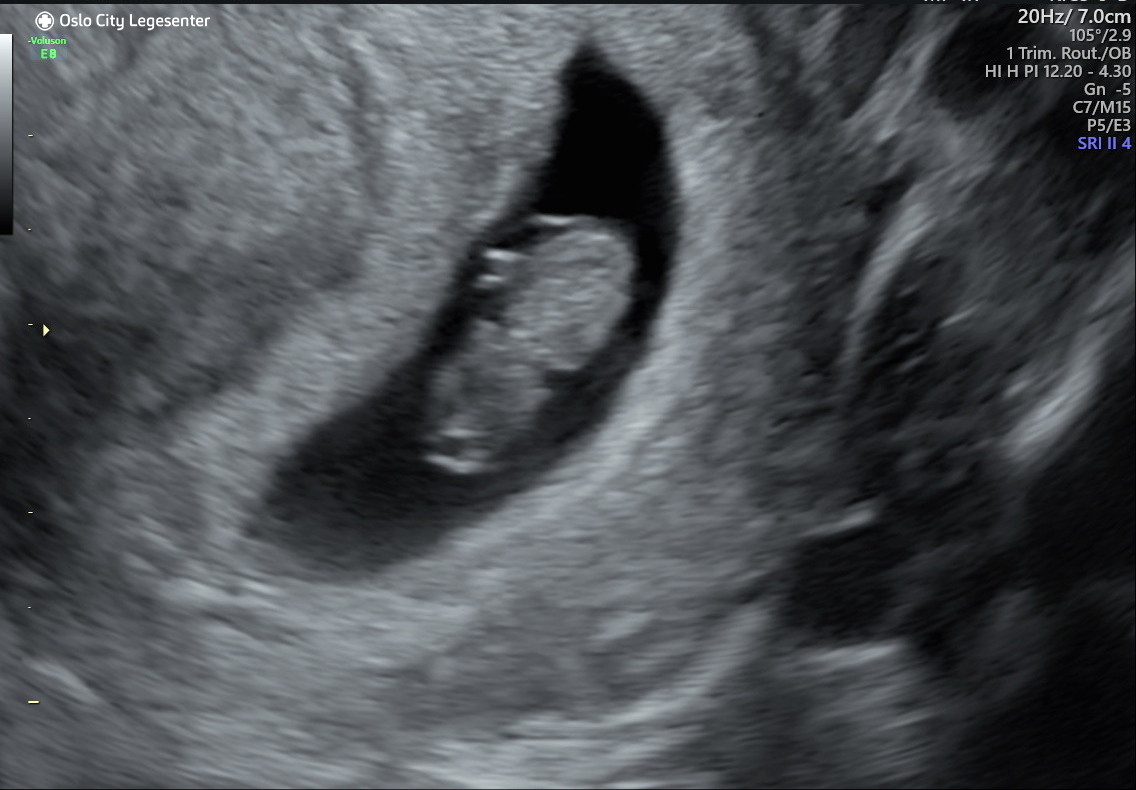

5+4

Titter bare innom for å si at jeg skal på TUL i morgen. Skulle egentlig i starten av februar men måtte avlyse timen, og siden gynekologen hadde så full kalenderen lurte hun på om jeg ikke ville komme i morgen siden da hadde hun fått en avbestilling. Antar at det ikke er så altfor mye å se, men håper jeg ser en «liten forlovelsesring». Finner trolig også ut av hvilken livmor det er snakk om og om det er flere der inne. Håper jeg får se hjertet slå også, men er forberedt på at det kan være for tidlig, og skal prøve å ikke bli redd hvis man ikke ser det.